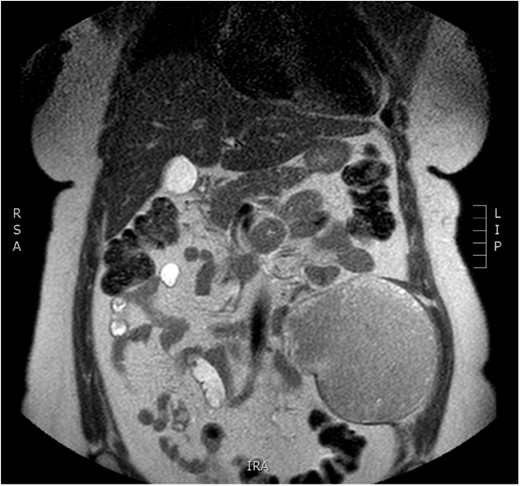

Physical examination revealed a painless, mobile parietal mass on the left anterior abdominal wall, more prominent during cough, of ~13 cm in diameter, with smooth contour and without skin involvement. Laboratory examination including cancer marks showed results within normal limits; hydatid serology (IgG antibodies) was also negative. As ultrasonography results were inconclusive, further imaging with magnetic resonance imaging (MRI) revealed a sizable cystic mass measuring 10 × 13.4 × 11.7 cm, located in the left anterior abdominal quadrant, in the paraumbilical region, between the left internal oblique and the transversus oblique muscle, with projection to the inferior surface of the rectus abdominis. The mass was characterized as a thin-walled cystic lesion, with delayed uptake of intravenous contrast of the wall. High signal intensity was observed on T1-weighted images and low signal intensity on T2-weighted images, with high probability of neoplasia or bleeding (Figs 1–3). No other abdominal or pulmonary lesions were present.

Preoperative MRI. T2 weighted image. Low sign density of the lesion.